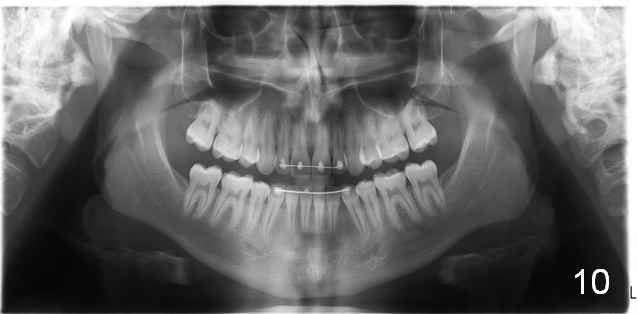

Maxillary Retrusion Post-Orthodontic Treatment

Initial information was obtained on 02/26/2014 (Fig.1-10). Anterior edge-to-edge and Posterior Open Bite (Fig.4 *): unfavorable differential Class III growth after orthodontics as a child.